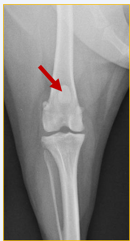

What does this radiograph show?

Cranio-caudal stifle joint

What is the centre point of this radiograph?

Stifle joint

What are the collimation borders for this radiograph?

Distal femur, proximal tibia and fibula, lateral skin edges

Is there anything missing on this radiograph (radiograph created using a computed radiography system) ?

Right/left marker

What anatomical structure is the red arrow pointing to?

Patella